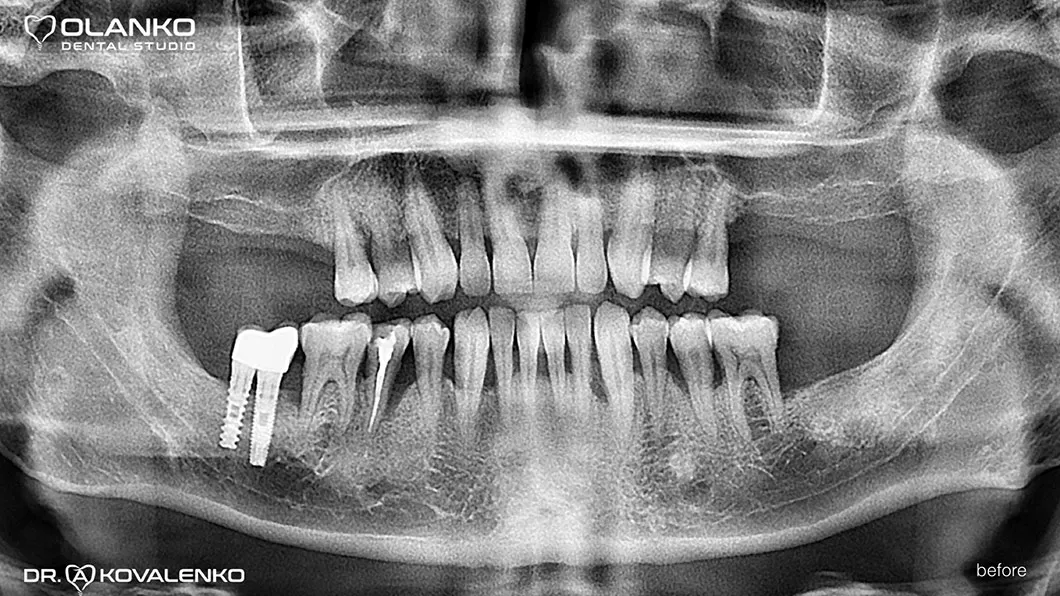

Пациент обратился с жалобами на отсутствие жевательной группы зубов.

Лечение: операция костной пластики на верхней челюсти (двухсторонний синус-лифтинг). Установка 4-х зубных имплантатов на верхней челюсти и один зубной имплантат на нижней челюсти. Пластика мягких тканей в области имплантатов.

Ситуация до

До и После:

до